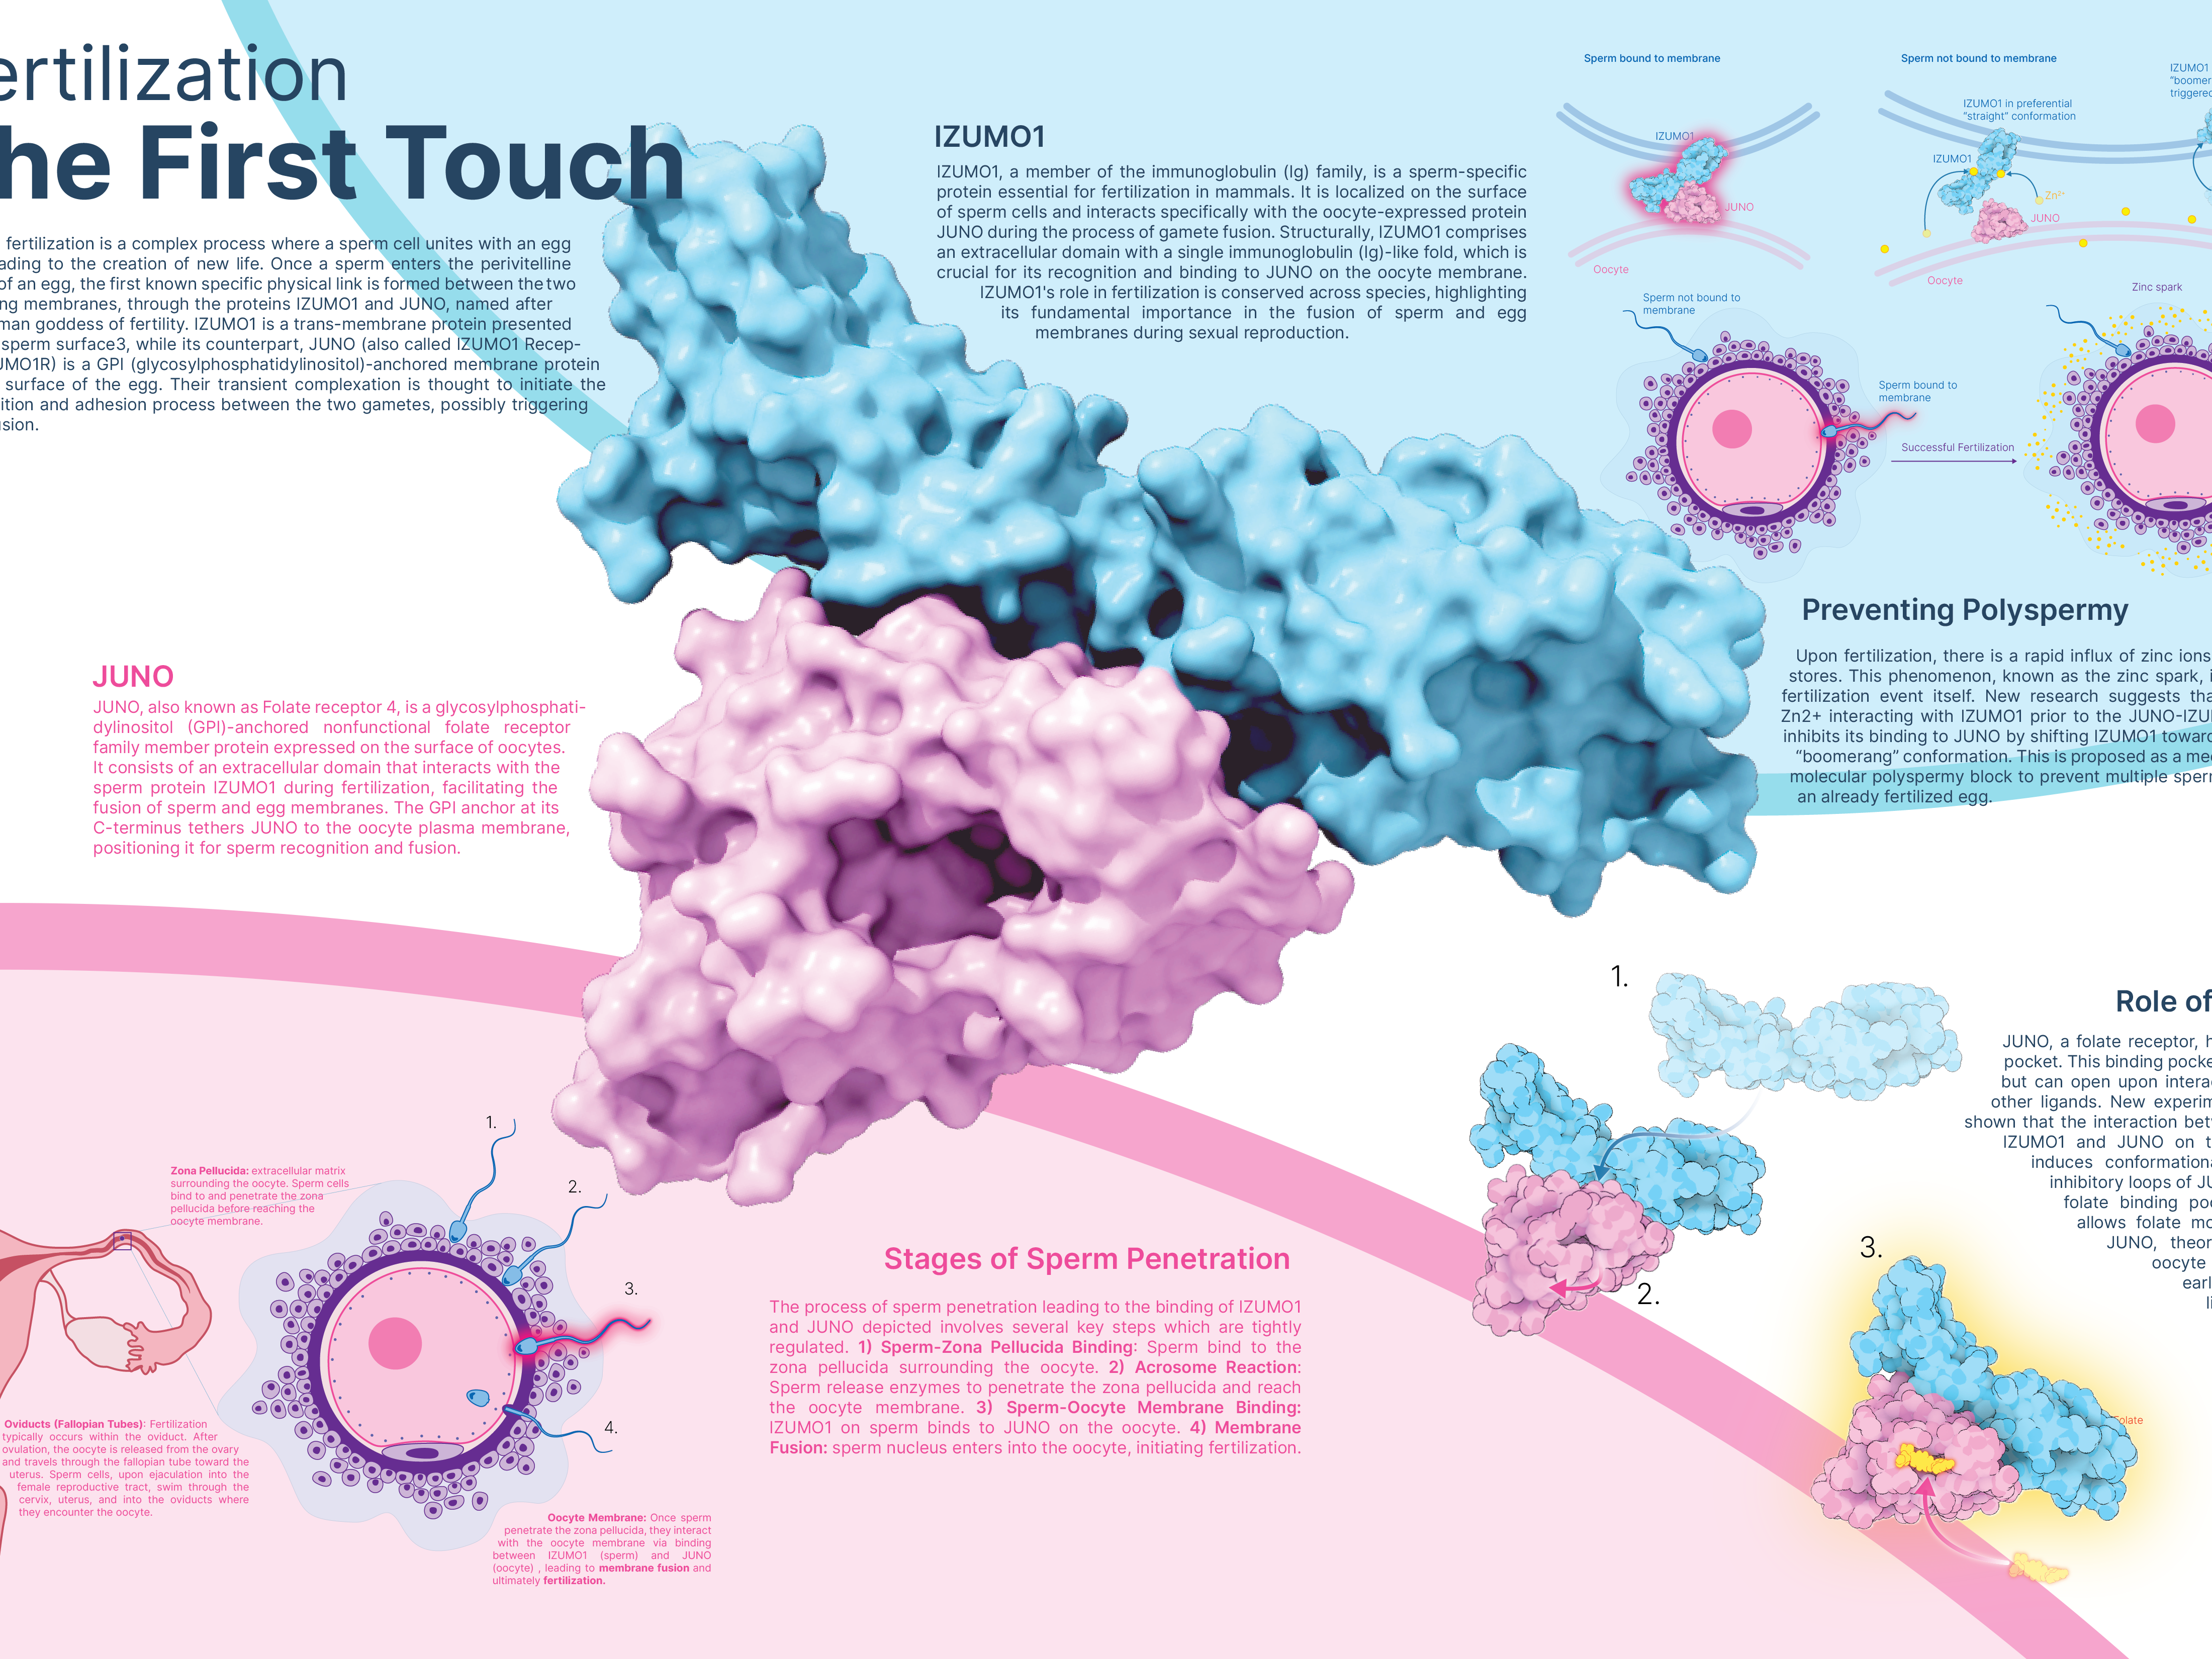

Fertilization: The First Touch

2024

3D Molecular Vizualization | Photoshop, Illustrator | Client: Derek Ng